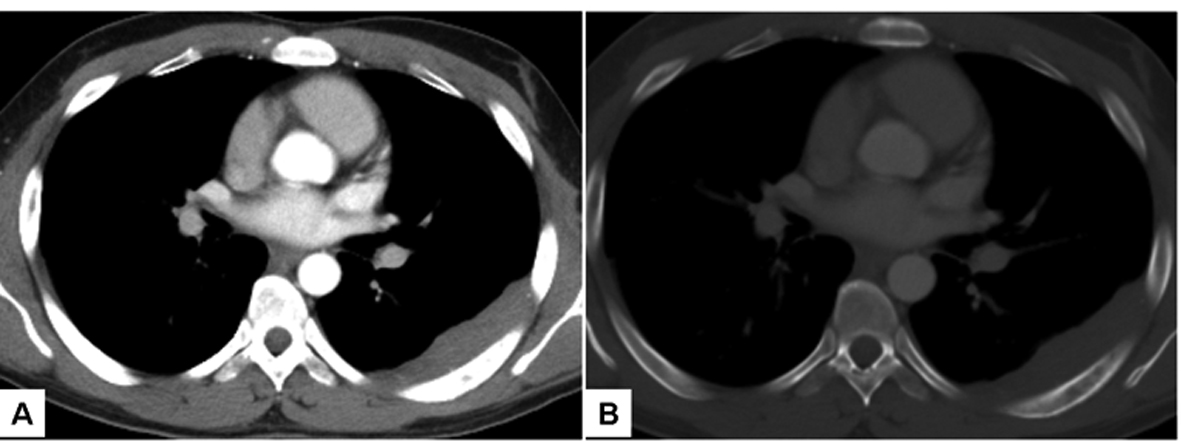

The patient was a 28-year-old male from Jewish-Ethiopian descent, with no history of chronic diseases. He presented with right eye pain lasting for three weeks and loss of vision in the same eye. Fundoscopy showed bilateral papilledema and unknown cells within the vitreous. A brain MRI showed enhancement of the pituitary infundibulum and thickening of the optic nerves and optic chiasm, as well as an enhancing lesion in the pineal gland (Fig. 1). Whole body CT scan showed a left sided chest wall lesion with destruction of the 6th rib (Fig. 2). Tumor markers, including beta-HCG, alpha-FP, were within the normal limits. Since the differential diagnosis of the CNS lesions included sarcoid, angiotensin and calcium levels in the blood and CSF were examined and found to be within the normal limits. Repeated CSF examination showed normal biochemistry, and cytotyping of lymphocytes from the lumbar puncture was compatible with reactive lymphocytes; malignant cells were not demonstrated. CSF was negative for CMV DNA, Ig for West Nile virus, HHV-6 DNA, HSV-1 DNA, Varicella Zoster DNA. A core needle biopsy was taken from the pleural lesion and was consistent with poorly differentiated PNET with negative FISH and PCR for translucation (t 11; 22). The tumor cells stained positively via immunohistochemistry for synaptophysin and CD-56, but were negative for LCA, CD-20, CD-3, CD-43, TdT, PAX-5; vimentin, FLI-1; cytokeratin, Cytokeratin-7, Cytokeratin -20, P-63, and inconclusive for chromogranin. Bone marrow aspiration was normal without evidence of malignant cells. The possibility of taking a biopsy or cytology from the brain lesion or the vitreous was ruled out by the neurosurgeons and ophthalmologists in our institution, due to the high surgical risk.

![]() Click for large image | Figure 2. Axial CT images through mid-thorax demonstrate pleural-based soft tissue mass along the posterior aspect of the left hemithorax (A). On bone window (B), permeative destruction of the adjacent 6th rib is noted. |

On presentation, the patient was started on high doses of steroids with immediate improvement of his eyesight. After histological evidence of PNET, chemotherapy was started with etoposide-ifosfamide alternating with vincristine, doxorubicin and cyclophosphamide cycles. A brain MRI on the 4th day of the first chemotherapy cycle (and after two weeks of steroid treatment) revealed disappearance of the lesion in the pineal gland and partial resolution of the other CNS sites. The chest wall lesion regressed significantly after chemotherapy.